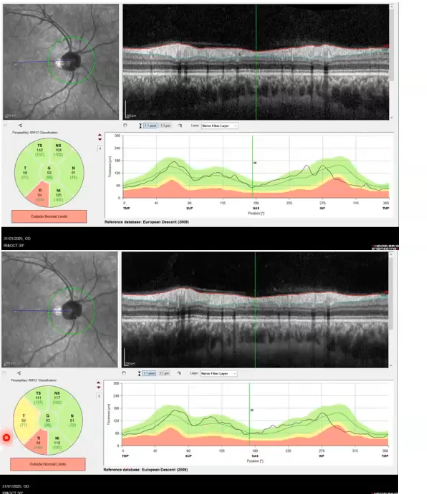

thickness comparison of cpRNFL

thickness compared to normative databse along its length and in sectors

inner limiting membrane and rnfl are the two easiest layers to segment

enables accurate measurements of thickness

right picture shows healthy eye. thicker nerve fibre layer in inferior temporal and superior temporal area

left; inferior temporal shows it is thinner as it drops off in graph.

what do the colours mean on comparisons to normative data

measurements are compared to those taken from a large number of healthy volunteers; called normative database

green= within normal limits= greater than 5th percentile of normative data

yellow= borderline, between the 1st abd 5th percentile

red= outside normal limits below 1st percentile of normative data